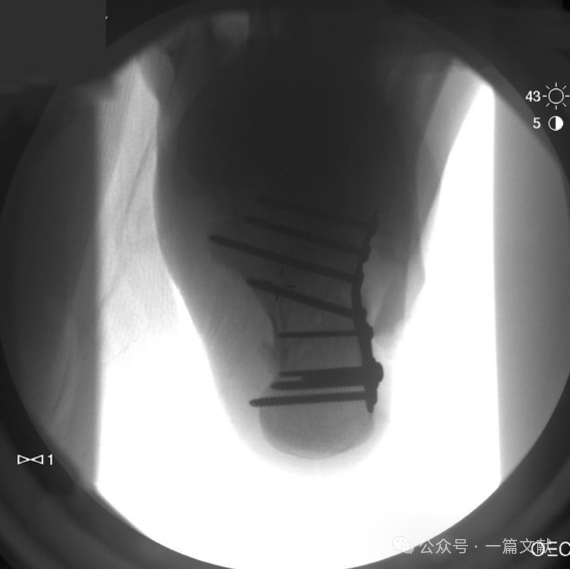

四,术中拍摄的各影像图如下:

3.1 跟骨侧位片:可观察Bohler’s角,Gissane角,后距关节面情况,以及跟骨结节的移位情况,如下图:

可用于评估(1)跟骨高度,(2)跟骨长度,以及(3)后距关节面的受累,如下图: